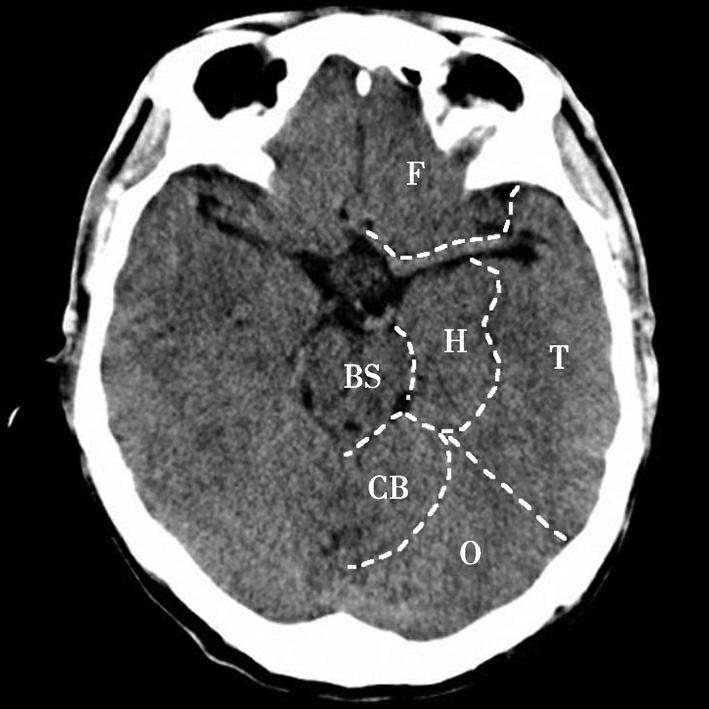

图1-2-17 脑叶划分示意图

CB.小脑;BS.脑干;T.颞叶;F.额叶;O.枕叶;H.海马回及海马结构

鞍上池位于层面的中部,多数呈六角星形,其前角连大脑纵裂池、两个前外侧角通外侧裂池、两个后外侧角延续为环池,后角为中脑双侧大脑脚之间的脚间池。鞍上池的六条边为前面的两侧额叶底部、外侧边为颞叶钩回,后两条边为大脑脚。如后方为脑桥,则鞍上池呈五角星形。鞍上池内前部有视交叉、视束及漏斗,两侧有颈内动脉。乳头体位于鞍上池后部中脑前方。鞍上池两侧为颞叶,颞叶内侧前部为杏仁体,杏仁体后方为海马,海马内后方向内突出的脑回为海马旁回,海马外侧可见侧脑室颞角。在颞叶前方通过外侧裂池与额叶相隔。鞍上池后方为中脑、中脑后部的中脑导水管及中脑两侧的环池。